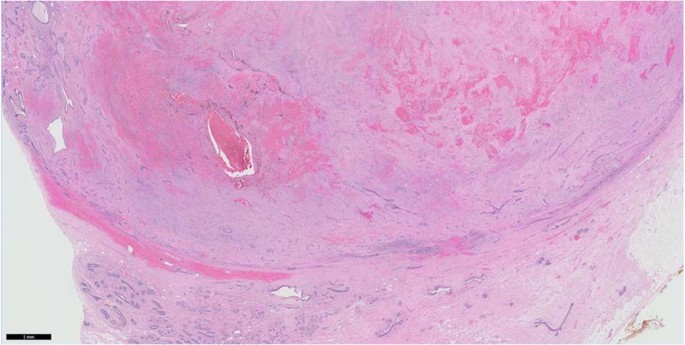

A variety of histological changes can be seen in the fibroadenoma. Infarction may occur in pregnant patients and post-instrumentation (Fig. 2). The fibroadenoma stroma is usually of low cellularity, with myxoid, fibroblastic or hyalinised appearances. Stromal multinucleated cells [4,5,6], calcifications, ossification and pseudoangiomatous stromal hyperplasia (PASH) may be present. The epithelium can display usual ductal hyperplasia (UDH), reported to occur in 32.3% of cases (excluding mild hyperplasia) [7], apocrine metaplasia, sclerosing adenosis, atypical ductal hyperplasia (ADH), atypical lobular hyperplasia (ALH), ductal carcinoma in situ, lobular carcinoma in situ and even invasive carcinoma [8] (Fig. 3), although the cancer rate in fibroadenoma is exceedingly rare, from 0.002 to 0.125% [9]. Carter et al. found a 0.81% prevalence of ALH or ADH in fibroadenomas, which when confined within the fibroadenoma, does not translate to a clinically meaningful increased risk of subsequent breast cancer development [10].